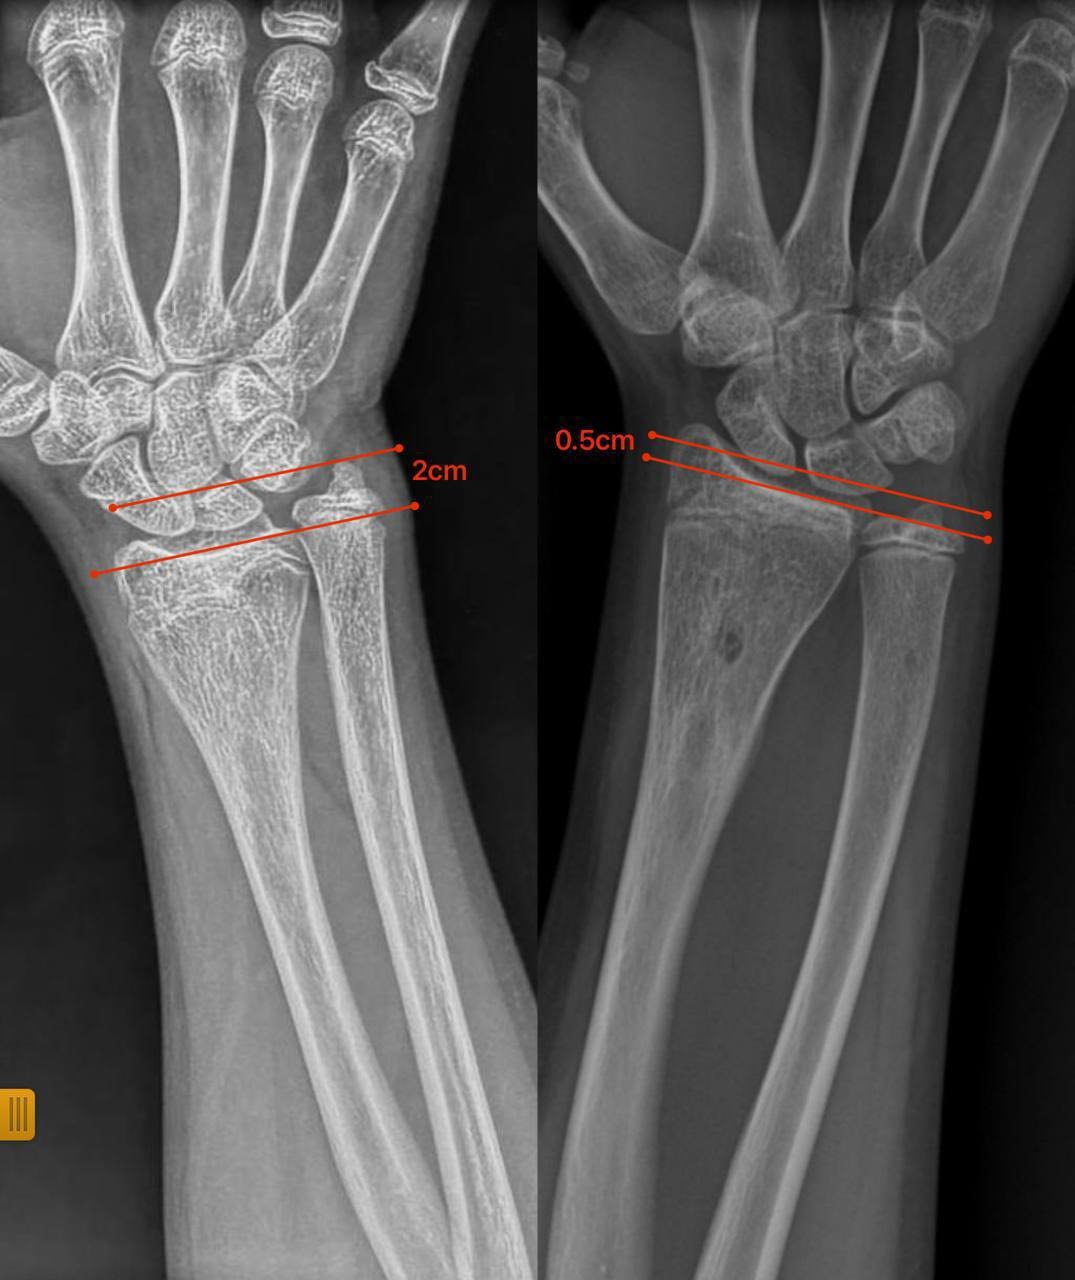

Нещодавно до відділення звернулися батьки 12-річної дівчинки з іншої області з післятравматичною деформацією кісток передпліччя. Лікарі виявили, що ріст кістки порушився через утворення кісткового мостика, який заважав росту кістки та деформував її.

Через сім місяців передпліччя дівчинки повністю відновило форму, ріст кістки нормалізувався, а рухливість кінцівки збережена.

Цей випадок демонструє, що не всі деформації потребують складних оперативних методик: іноді достатньо усунути першопричину порушення росту, щоб кістка розвивалася природним шляхом.